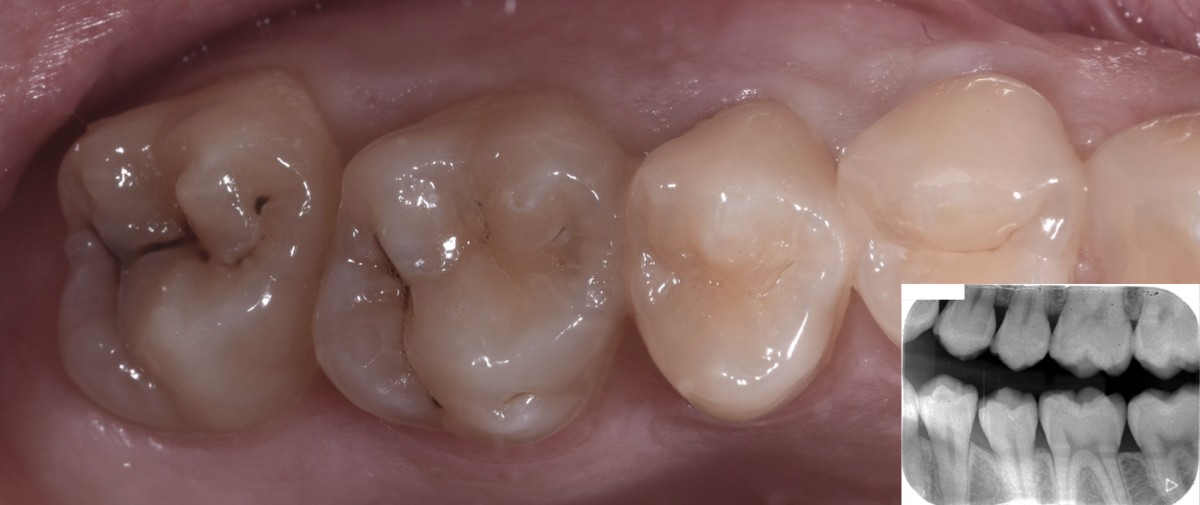

3 years follow up and final rx bitewings (Fig.10).